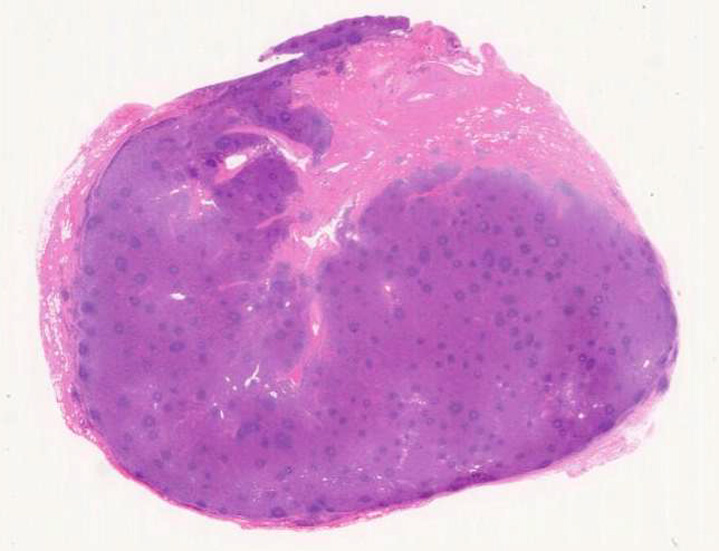

硝子血管型 hyaline vascular type: 臨床症状に関係なく3つの病理組織所見で診断が決まる。*1

1. 萎縮した胚中心をもつ異常な血管増生を示すリンパ濾胞(Lolli-pop follicles. Lolli-popはキャンディ-の名前のようです)

2. 濾胞間リンパ組織の線維化, 血管増生

3. 被膜は肥厚し, 少なくとも病変中心部ではsinuses(リンパ洞)を欠いている

- 肉眼的には弧在性腫瘤が最も多い。

- 濾胞と濾胞間組織の割合は症例によりさまざま。

- 濾胞は小型で周囲を広いmantle zoneで囲まれている。同心円状のよく発達したmantle zoneは「onion skin」と呼ばれる。濾胞は濾胞樹状細胞と進入血管の内皮から構成されている。ときに大型奇異,「異形」細胞が見られるが異常な濾胞樹状細胞と考えられる。-> Dr. Castlemanが「Hodgkin diseaseとの鑑別が必要」といった症例がこのような例に相当すると考えられる(Dr.小島)

「広いmantle zoneの取り巻いたリンパ球の少ないFDCのめだつ小さな濾胞, 硝子化することもある, 濾胞間は細血管でいっぱい」がkey word